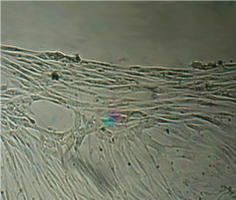

Монослой оставался целостностным и равномерным на всей поверхности чашки Петри, клетки вблизи образца сохраняли характерное для культуры фибробластов взаимное расположение и направление роста (рис. 39).

Морфология их также соответствовала сроку роста: клетки веретеновидной формы с гомогенной цитоплазмой и центрально расположенным пузырьковидным ядром неплотно прилежали друг к другу и анастомозировали своими отростками.

В последующие сроки мы также не наблюдали каких-либо морфологических признаков воздействия имплантата на культуру фибробластов.

Клетки формировали равномерный монослой, плотность которого соответствовала сроку роста культуры после пассирования и не зависела от расстояния до образца (таб. 17).